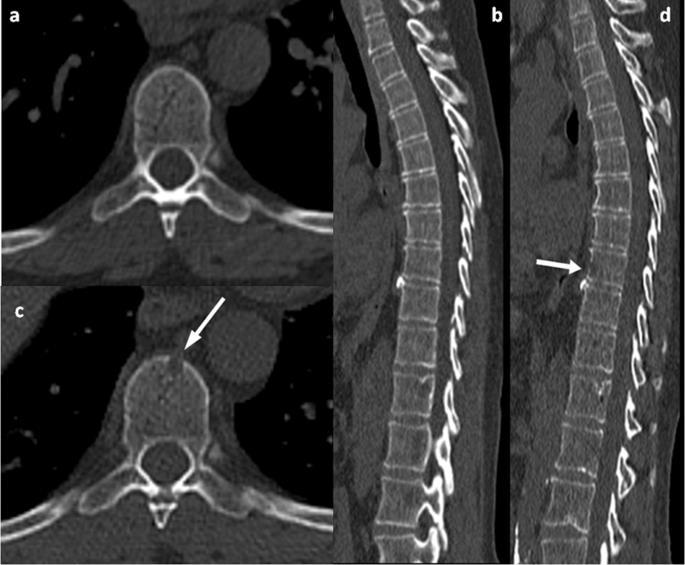

Imaging for Multiple Myeloma

Image: Gavriatopoulou M, et al. Blood Cancer J. 2020;10:93

SEVERAL OPTIONS FOR BONE IMAGING

Whole Body LowDose CT (WBLDCT)

Best for early screening for bone disease

PET-CT MRI Whole body (WB) or spine + pelvis

Response assessment: active residual disease Gold standard to assess bone marrow involvement

Skeletal survey is no longer the standard of care in MM

Bone scan (DEXA) for bone density is not for MM

CT = computed tomography; DEXA = dual-energy x-ray absorptiometry; MM = multiple myeloma; MRI = magnetic resonance imaging; PET = positron emission tomography; WB = whole body; WBLDCT = whole-body low-dose computed tomography.

Whole Body PET-CT FDG-avid lesions: T10-T12, L2, lateral right ribs; right humerus

Whole Spine MRI T10-T12 lesions, L2 lesion, intact spinal canal